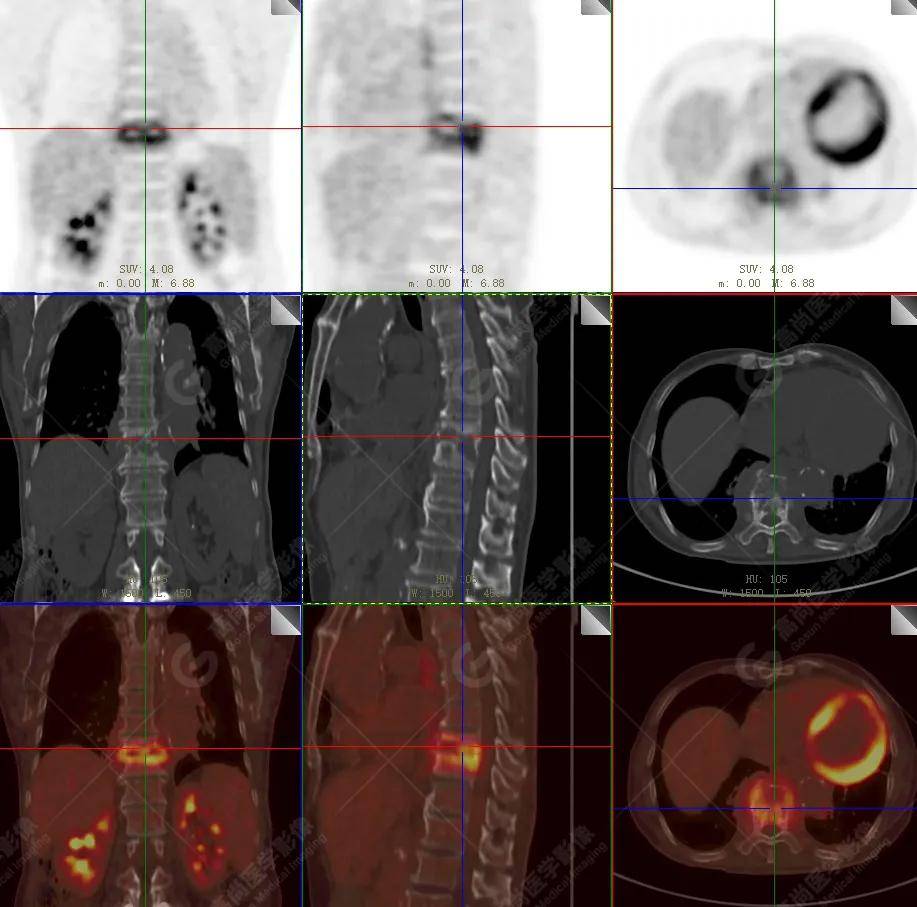

【高尚病例】18f-fdg pet/ct显像应用于骨结核

图片尺寸919x854